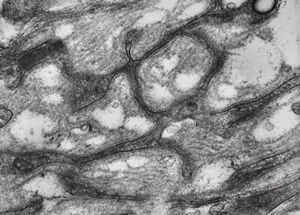

M,15y. | neurinoma - orbita